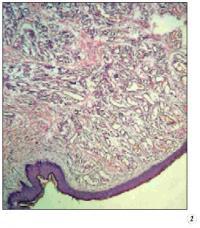

Отмененная опухоль